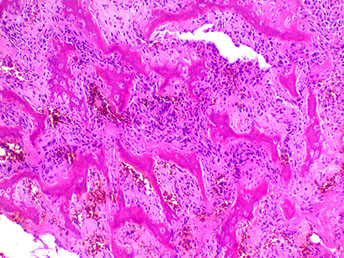

Hyperparathyroidism - Brown tumors. Right image shows zone of bone resorption in center c defect filled c fibroblastic tisuue, and around the periphery is osteoid-producing area that looks like fibrous dysplasia. Image on left is close of area replacing fibroblastic tissue c lots of osteoclast-like GCs, that may lead to misdiagnosis of giant cell tumor (except GC tumors usually lack fibrogenic stroma)

Brown Tumor

Bone loss causes microfractures and hemorrhage causing macrophage influx and reparative fibrous tissue

Brown from vascularity, hemorrhage and hemosiderin deposition

"Brown tumors" of bone are caused by hemorrhage and hyperparathyroidism

- may also be caused by pseudohyperparathyroidism, but is usually due to parathyroid adenoma, hyperplasia, or rarely carcinoma or chronic renal failure

Micro: Osteoclasts line cystic spaces (tunneling), which also have a very fibrous stroma, inc formation of woven bone, and peritrabecular fibrosis, MNGCs